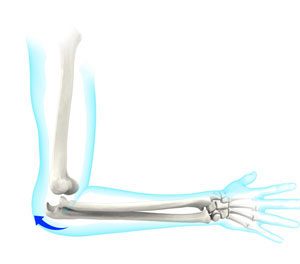

The elbow is a complex synovial hinge joint consisting of an articulation between the distal humerus and proximal ulna (humeroulnar joint), distal humerus and proximal radius (humeroradial joint), and the ulna and radius (radioulnar joint)3. The humeroulnar joint is responsible for flexion and extension of the elbow3. The humeroradial joint and the radioulnar joint are responsible for pronation and supination of the forearm3.

Normal anatomy of the elbow bones4.